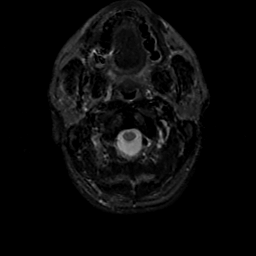

MR Study #19, August 25, 1991 -- Slice #0